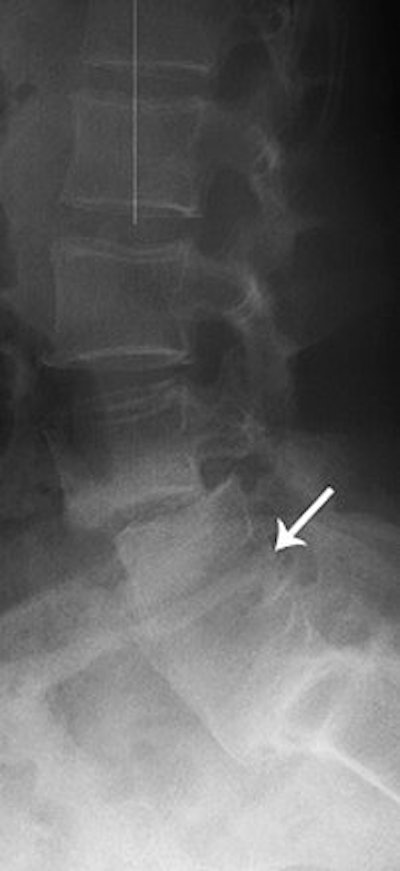

| A 65-year-old woman with history of L4-L5 fusion and anterolisthesis of L3-L7. Sagittal multiplanar reconstruction shows complete fusion (arrow). |

| Lateral radiograph shows partial fusion. Krestan CR, Helge H, Vasilevska V, Weber M, Schueller G, Imhof H , and Czerny C, "MDCT Versus Digital Radiography in the Evaluation of Bone Healing in Orthopedic Patients" (AJR 2006; 186:1754-1760). |